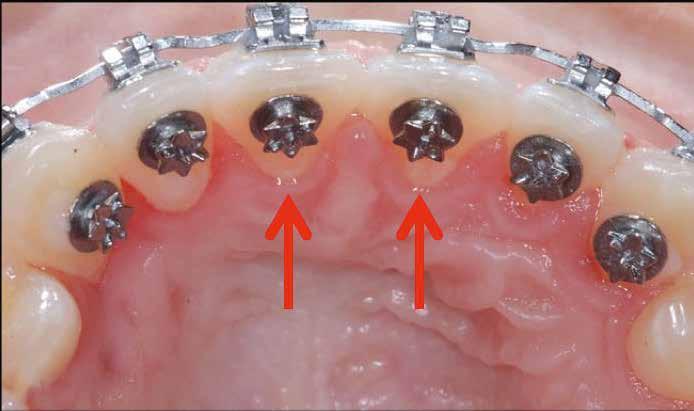

A hiányzó oldalsó kismetszők részárással történő kezelése során a szemfogak és oldalsó fogak meziális mozgatása közben a fogszabályozó orvosnak csiszolással kell a fogak formáját igazítani. Már a kezelés elejétől a szemfog elcsiszolása nem csak az incizális részre kell hogy kiterjedjen, hanem az approximális, palatinális és a vesztibuláris felszín éli negyedére is. Így érhetünk el egy rövidebb klinikai koronát, a vesztibulo-orális méret csökkenését, egy incizális élet, valamint a szemfog megfelelő pozicionálását a kismetsző helyén. A túl széles szemfog megakadályozza a megfelelő interkuszpidáció kialakítását az oldalzónában. A palatinális felszín elcsiszolásával biztosítjuk az interferenciák nélküli metszővezetést, és a megfelelő overjetet a frontfogak enyhe érintkezésével. Ha a szemfogra a későbbiekben esztétikai pótlás készül, a megfelelő approximális elcsiszolás (az esztétikai fogorvossal történő egyeztetés után) biztosítja a zenith kívánatos pozícióját a későbbi felépítéshez. A mezializált kisőrlő palatinális csücskének elcsiszolására csak akkor van szükség, ha ez akadályozza a megfelelő fogérintkezést. Az első kisőrlő mindkét csücske fontos a már a szemfog helyén álló fog esztétikai és funkcionális beállításához.

A szemfog oldalsó kismetsző helyére történő bemozgatása során a fog átalakítása javasolt a két fog eltérő morfológiai adottságai miatt (1. a-b. ábra). A fog kontúrozása, vagy úgynevezett formázása magába foglalja az approximális felszínek elcsiszolását, valamint a többi fogfelszín igazítását a kívánt fogformának megfelelően [1].

Szemfog becsiszolás

A szemfog elcsiszolásához piros gyémántfúró javasolt, finom szemcsézettséggel, 27-76 µm (okkluzálisan lekerekített – Rodentica, speciális hegyű 806314466514031, Komet 8833), gyorsítóval (max 160 000 fordulat/perc) megfelelő hűtés mellett, legalább 50 ml/perc. Ezt követi a felület kidolgozása és polírozása sárga gyémántcsiszolóval, extra finom szemcsézettséggel, 10-36 µm (Rodentica 806314466504031) és narancssárga Sof-Lex korongokkal (finom alumínium-oxid szemcsék 3-40 µm, extra finom, narancssárga-sárga, alumínium-oxid kristályok mérete 1,7 µm) könyökdarabban (25000 fordulat/perc) megfelelő hűtés mellett min. 50 ml/perc (2. a-d. ábra).

Kisőrlő becsiszolása

Ha a szemfog helyére mezializált kisőrlő intrúziójára nincs is szükség, a palatinális csücsök akkor is akadályozhatja a harapást és a szemfogvezetést [44]. Ezekben az esetekben elcsiszoljuk a palatinális csücsköt (8. a-b ábra) piros gyémántcsiszolóval (finom, 27-76 µm, éli formázóval – Rodentica speciális tűhegy 806314466514031, Komet 8833 vagy GD – lándzsa Rodentica 806314257514020, Komet 0640) gyorsítóban (max 160 000 fordulat/perc) vízhűtés mellett, min. 50 ml/perc [39]. Extra finom sárga gyémántcsiszolóval polírozunk, 10-36 µm szemcsézettséggel (sárga éli csiszoló Rodentica speciális tűhegyű 806314466504031, GD – sárga lándzsa alakú Rodentica 806314257504020) és narancs Sof-Lex korongokkal (3M finom, narancssárga-alumínium-oxid kristály 3-40 µm nagysággal, extra finom, narancssárga-sárga, 1-7 µm alumínium-oxid kristályokkal) könyökdarabban (25 000 fordulat/perc) legalább 50 ml/ min. hűtéssel. Az elcsiszolást több lépésben végezzük, és ezt helyi fluoridalkalmazás követheti.